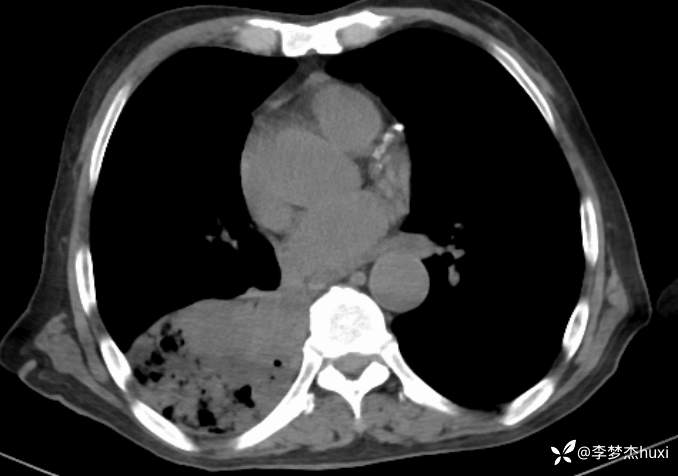

【现病史及既往史】: 1.患者老年 男,患者缘于3小时前无诱因出现意识不清,伴咳嗽、咳痰,痰不易咳出,伴发热,最高体温不详,院外应用“退热药物”(具体不详)治疗,无恶心、呕吐,无大小便失禁,无胸痛,今为求进一步治疗来院就诊,急诊查胸部及头CT:双侧基底节区腔隙性脑梗塞,脑白质稀疏,脑萎缩,脑干密度不均匀,右肺感染首为考虑,占位待除外,建议治疗后复查,右肺中叶局限性炎症,双肺间质性改变,主动脉及冠状动脉钙化,双肺气肿,左肺实性结节,建议复查,纵隔内及右肺门结节,右肺门增大。右肺下叶部分支气管堵塞。右侧胸膜局部增厚并少量积液,甲状腺密度不均匀,胆囊结石,右肾类圆形囊性密度影,建议结合超声。查血常规:白细胞数目 13.91*109/L,BNP前体 1360pg/ml。D-二聚体 0.8pg/ml。以“肺炎”收住院;。

4.辅助检查:急诊查胸部及头CT:双侧基底节区腔隙性脑梗塞,脑白质稀疏,脑萎缩,脑干密度不均匀,右肺感染首为考虑,占位待除外,建议治疗后复查,右肺中叶局限性炎症,双肺间质性改变,主动脉及冠状动脉钙化,双肺气肿,左肺实性结节,建议复查,纵隔内及右肺门结节,右肺门增大。右肺下叶部分支气管堵塞。右侧胸膜局部增厚并少量积液,甲状腺密度不均匀,胆囊结石,右肾类圆形囊性密度影,建议结合超声。查血常规:白细胞数目 13.91*109/L,BNP前体 1360pg/ml。D-二聚体 0.8pg/ml。。

美罗培南治疗无好转,并出现右侧胸腔积液,可能的病原菌?